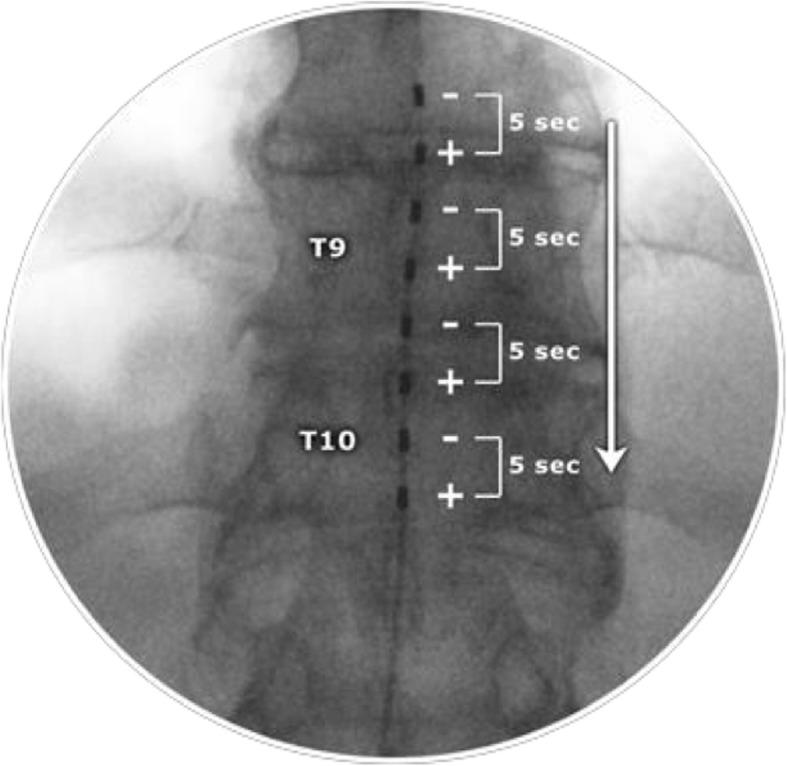

This is a multicentre, double-blind, randomised, sham-controlled trial with a parallel economic evaluation. A total of 96 patients with CNLBP who have not had spinal surgery will be implanted with an epidural lead and a sham lead outside the epidural space without a screening trial. Patients will be randomised 1:1 to 10 kHz SCS plus usual care (intervention group) or to sham 10 kHz SCS plus usual care (control group) after receiving the full implant. The SCS devices will be programmed identically using a cathodal cascade. Participants will use their handheld programmer to alter the intensity of the stimulation as per routine practice. The primary outcome will be a 7-day daily pain diary. Secondary outcomes include the Oswestry Disability Index, complications, EQ-5D-5 L, and health and social care costs. Outcomes will be assessed at baseline (pre-randomisation) and at 1 month, 3 months and 6 months after device activation. The primary analyses will compare primary and secondary outcomes between groups at 6 months, while adjusting for baseline outcome scores. Incremental cost per quality-adjusted life year (QALY) will be calculated at 6 months and over the lifetime of the patient.

这是一项多中心、双盲、随机、假对照试验,并进行平行的经济评估。共有 96 名未接受过脊柱手术的 CNLBP 患者将接受硬膜外导联和硬膜外空间外的假导联植入,无需进行筛选试验。在接受完整植入物后,患者将以 1:1 的比例随机分为 10 kHz SCS 加常规护理(干预组)或假 10 kHz SCS 加常规护理(对照组)。SCS 设备将使用阴极级联以相同的方式编程。参与者将根据常规实践使用手持编程器来改变刺激的强度。主要结局将是为期 7 天的每日疼痛日记。次要结局包括 Oswestry 残疾指数、并发症、EQ-5D-5 L 和健康及社会护理成本。在设备激活后 1 个月、3 个月和 6 个月时评估基线(随机前)和基线后结局。主要分析将在 6 个月时比较两组的主要和次要结局,同时调整基线结局评分。将在 6 个月时和患者的终生计算每增加一个质量调整生命年(QALY)的增量成本。